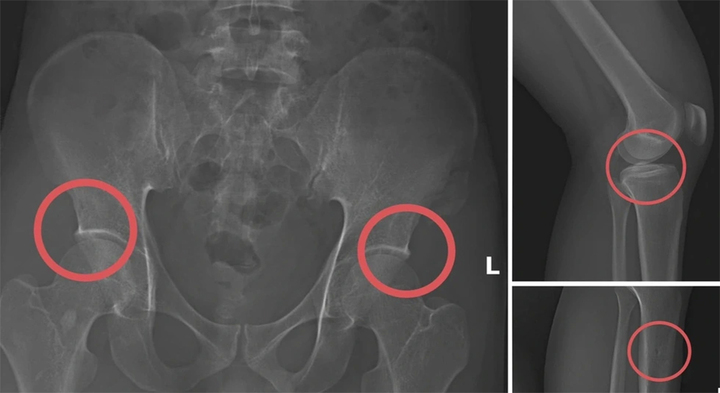

Tại đây, Châu tiêm thuốc mê vào tĩnh mạch của các đối tượng, sau đó dùng búa tác động trực tiếp vào các vùng xương chậu, xương đùi để tạo tổn thương nghiêm trọng.

Hình ảnh cho thấy các đối tượng tự gây thương tích nhằm trục lợi.